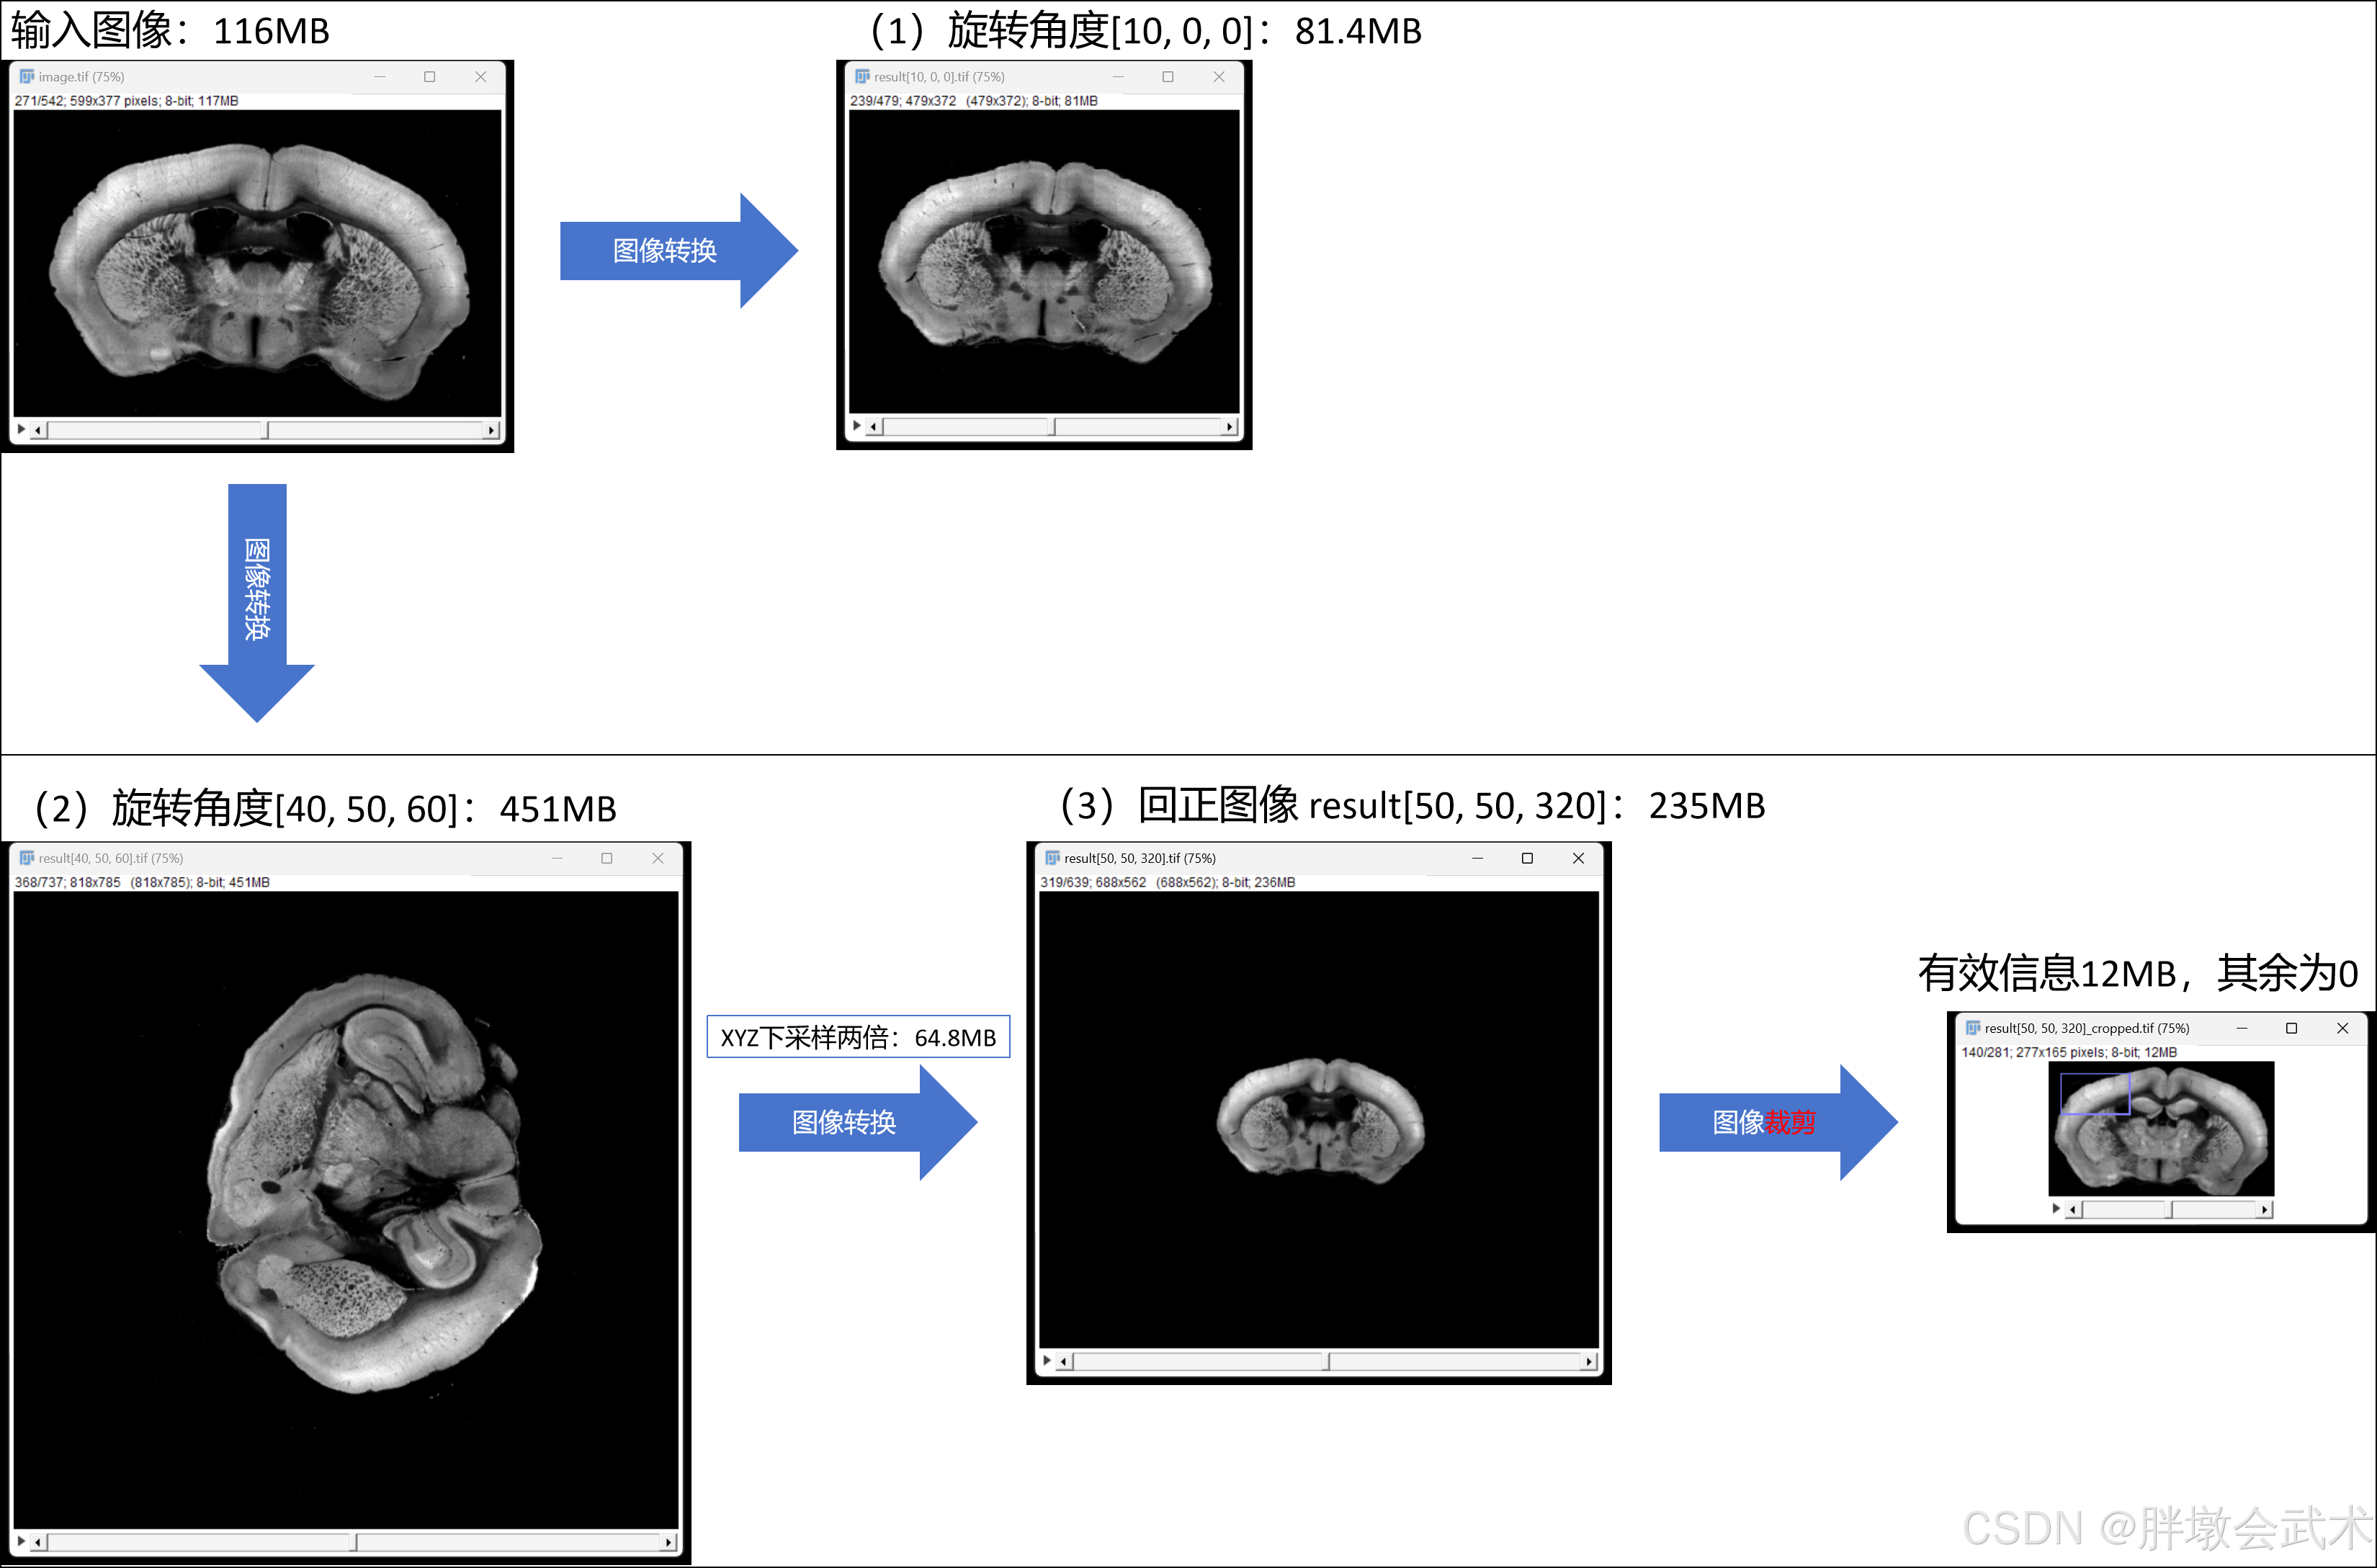

1.2.4、旋转图像 + 回正图像

虽然非固定坐标系,但反向旋转仍然是相对的、有效的操作。

在这里插入图片描述

输入具有旋转角度的3D图像,并回正 —— 最大支持XYZ旋转角度[0°,90°]

将具有旋转角度的3D图像沿着ZYX迭代旋转10度,然后计算回正图像(以冠状面为主)的最小ZYX角度。